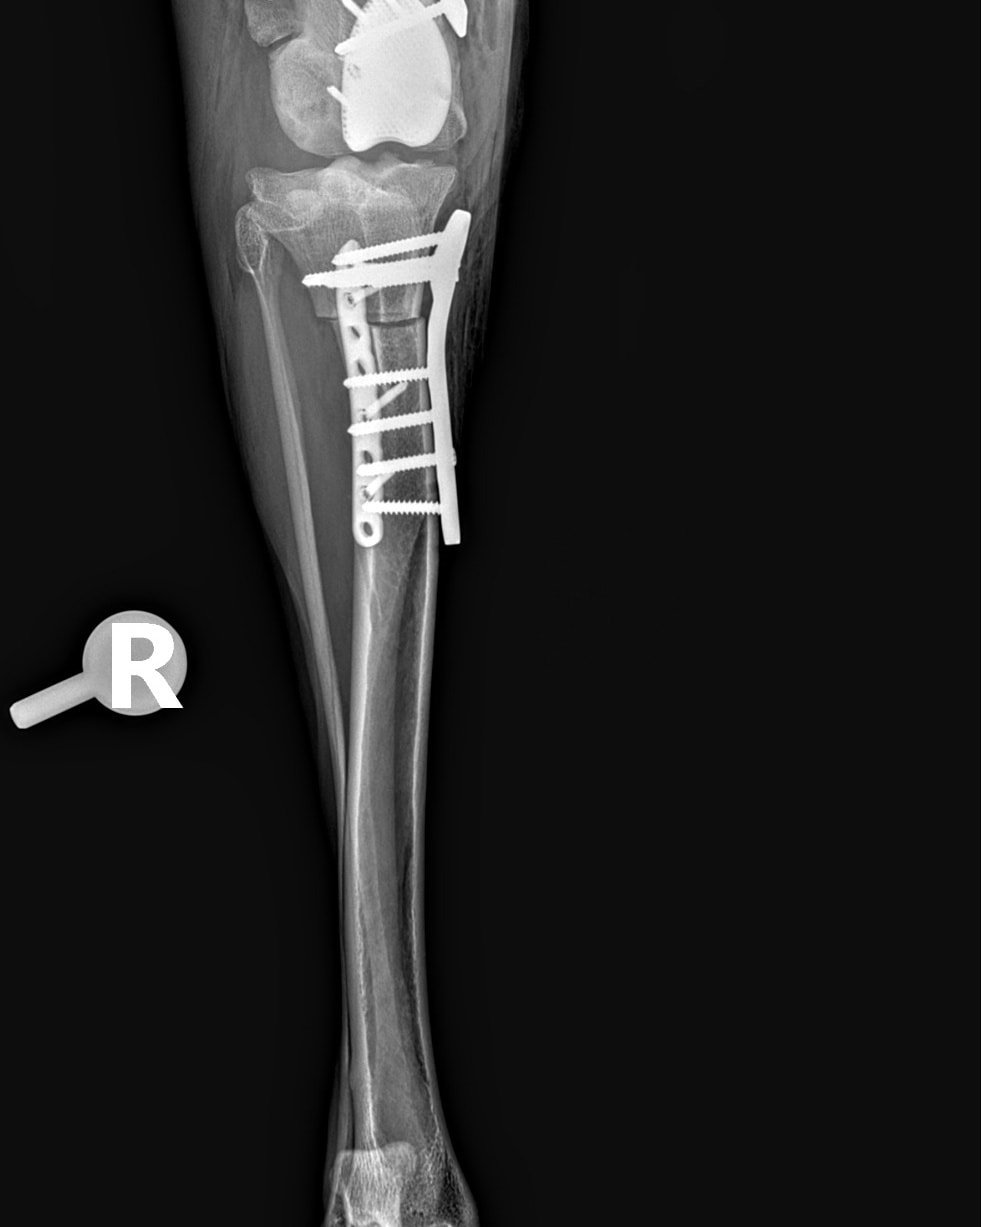

Abbiamo allegato fattura e lastre post-operatorie in totale trasparenza

CANGU è uno dei nostri grandi combattenti. Lo abbiamo salvato in Spagna molto tempo fa, quando viveva in condizioni disperate: grave dolore e difficoltà nei movimenti, zero prospettive senza un intervento immediato. Da allora abbiamo fatto tutto ciò che era possibile per offrirgli una vita degna. Abbiamo già finanziato due interventi complessi al primo arto posteriore:

– il primo intervento purtroppo non ha portato alcun miglioramento;

– il secondo, una protesi totale del ginocchio, ha finalmente dato risultati positivi e oggi quell’arto gli permette una migliore stabilità.

Ora ci troviamo di fronte ad passo indispensabile per garantirgli una qualità di vita accettabile: intervenire sul secondo arto posteriore, ancora in condizioni critiche. Lasciarlo così significherebbe condannarlo a un dolore costante, a un peggioramento progressivo con un carico eccessivo sulla prima protesi e a una vita senza autonomia. Operarlo, invece, significa dargli una possibilità reale di camminare meglio, di muoversi, di vivere dignitosamente. L’intervento previsto è un DFO con la protesi completa del secondo ginocchio. Il costo è di 8.098 euro (allegato preventivo). Non otterremo un cane “perfetto”: Cangu avrà comunque dei limiti, perché per un recupero totale servirebbero protesi anche a livello delle anche. Ma questo intervento rappresenta la parte fondamentale del suo percorso di riabilitazione, quella che può migliorare la sua quotidianità.